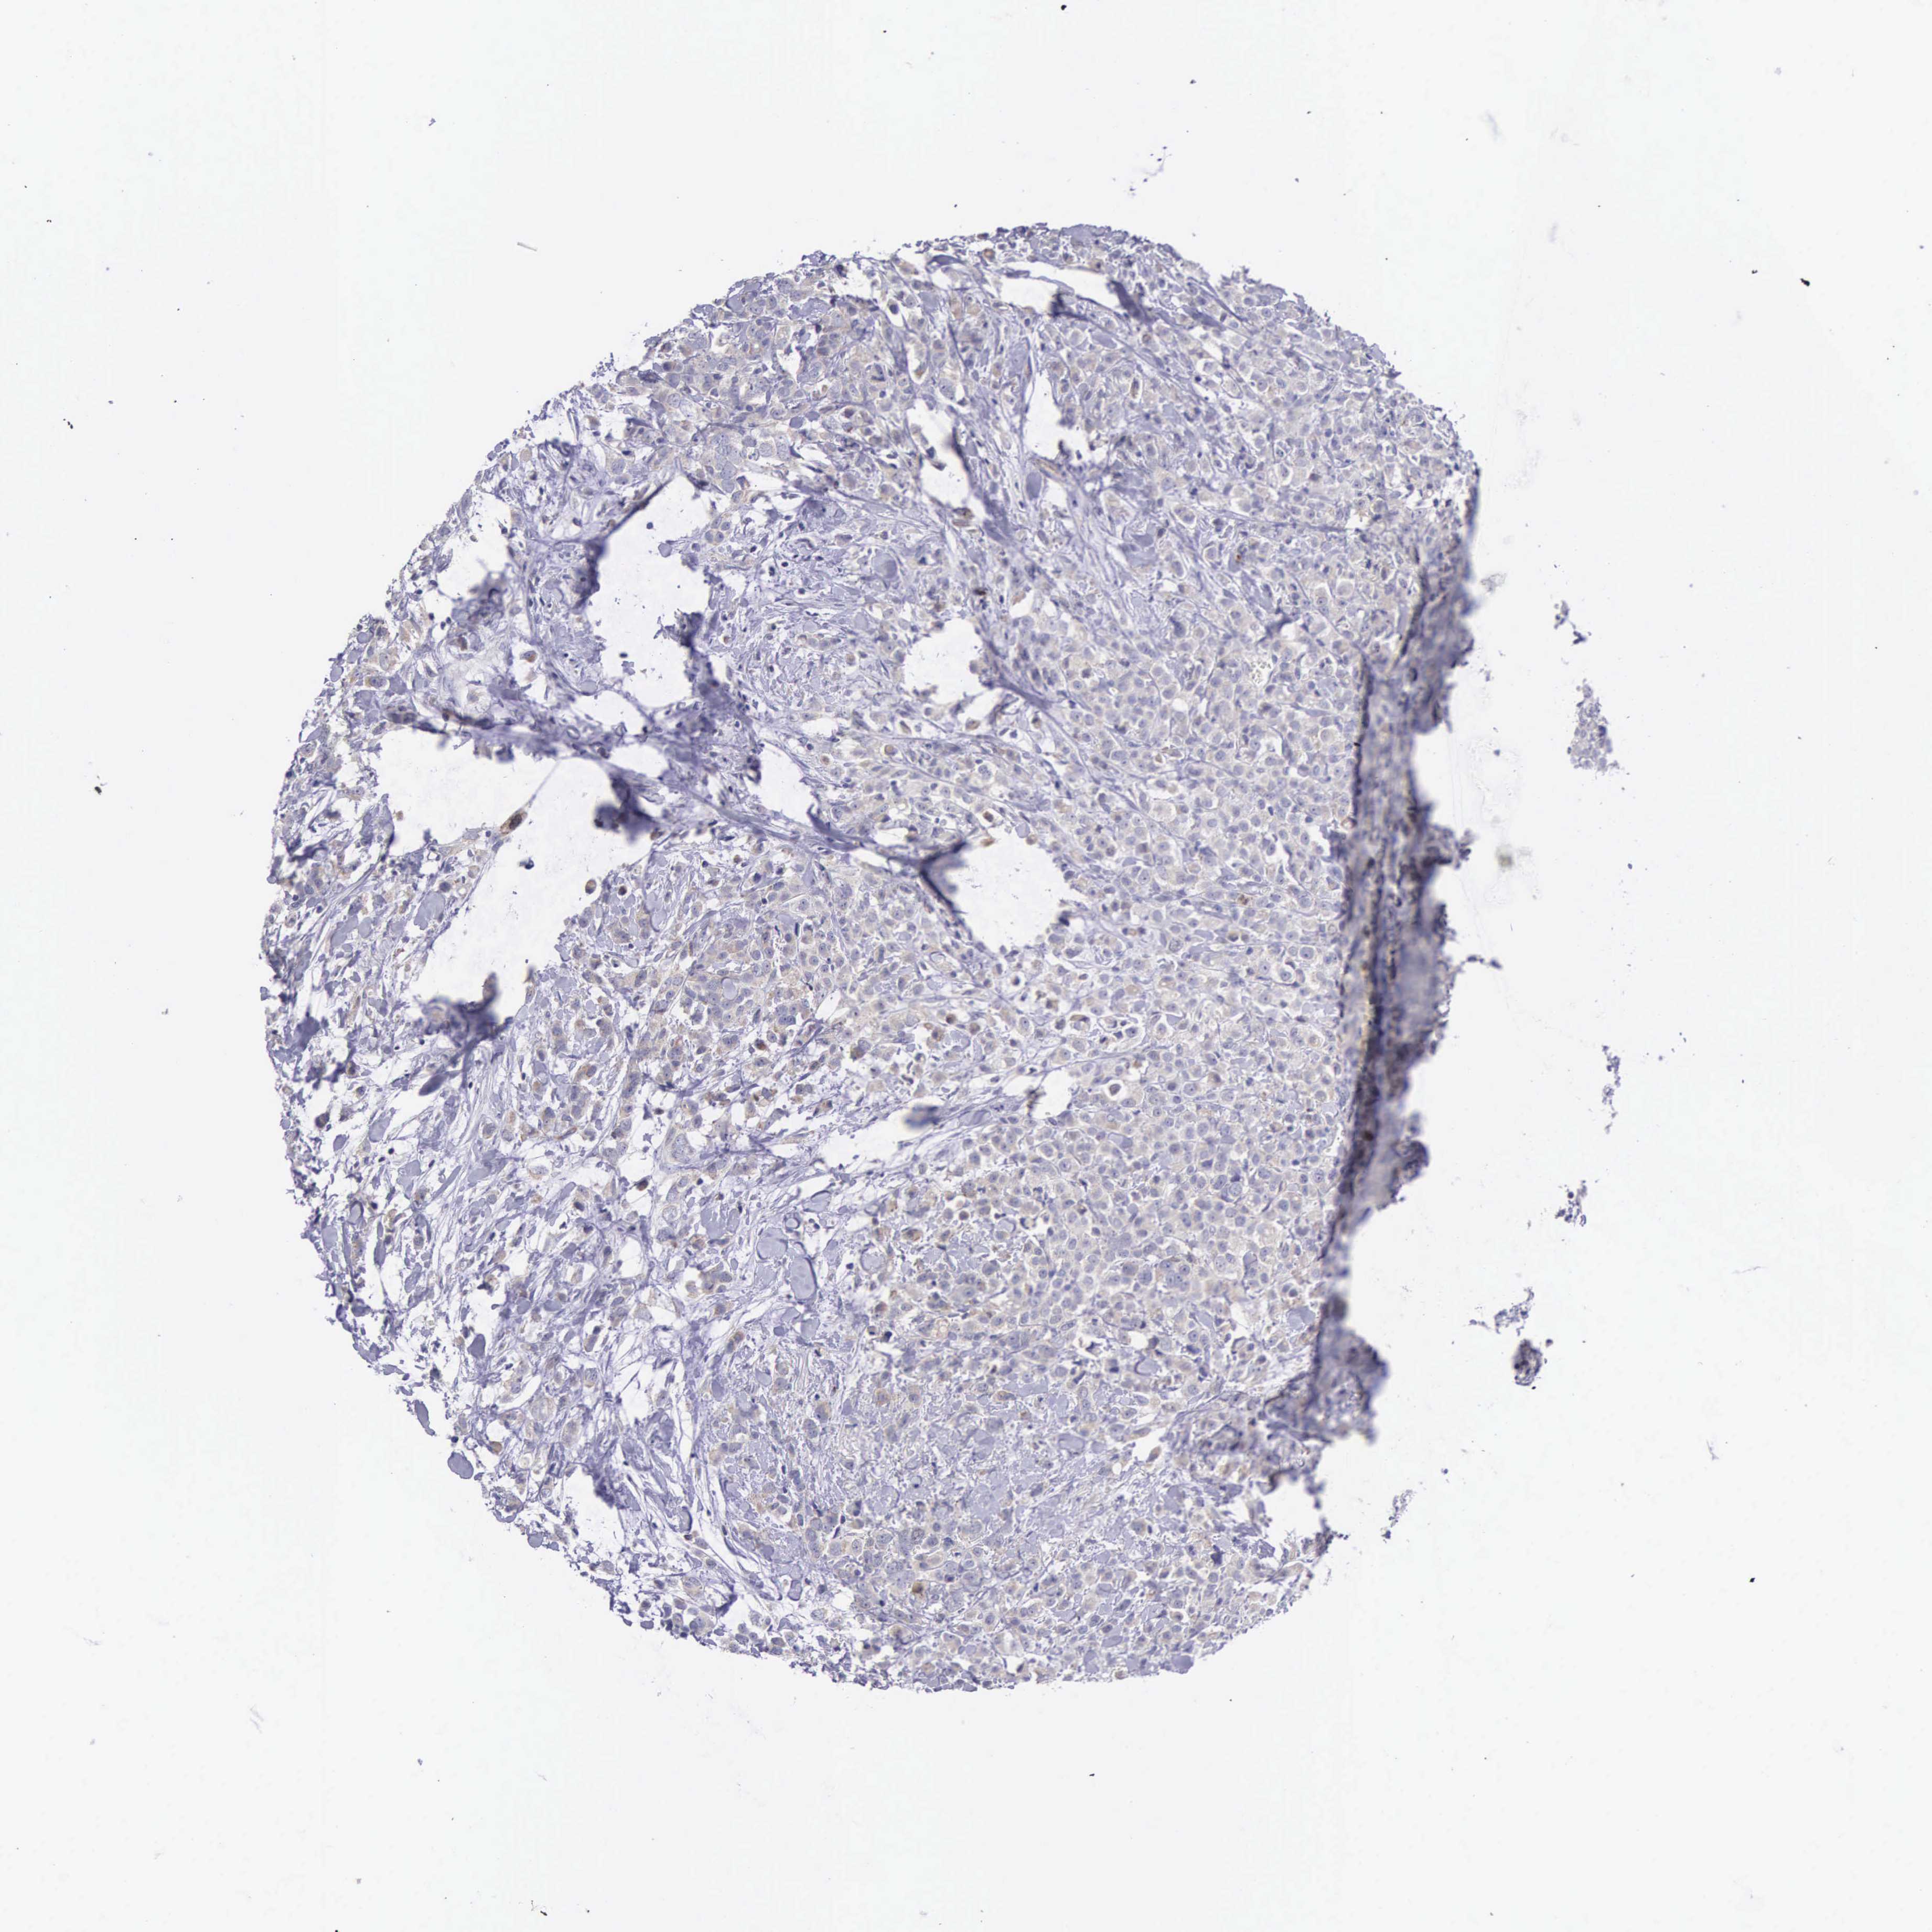

CANCER BREAST CANCER Show tissue menu

BRCA TCGA BRCA VALIDATION PROTEIN EXPRESSION

ANTIBODIES

AND

VALIDATION